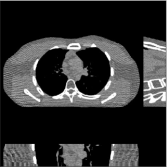

III-B3 Generalization Capability Comparisons between a “Denoising” Deep NN and the Proposed PWLS-ST- Method

This section compares the generalization capabilities between the proposed MBIR method, PWLS-ST-, and a denoising deep NN, FBPConvNet [14], that are trained from the phantom data; in particular, we tested the trained PWLS-ST- and FBPConvNet models to phantom and clinical scan data. The results in Fig. 6 show that the non-MBIR FBPConvNet method has higher overfitting risks, compared to the proposed PWLS-ST- MBIR method. When tested on clinical scan data, PWLS-ST- achieves much more accurate reconstruction, compared to FBPConvNet. See Fig. 6(b). When tested on phantom data, FBPConvNet generates more unnatural features as the number of views reduces, although it gives lower RMSE values compared to PWLS-ST-. See zoom-ins in Fig. 6(a). The FBPConvNet results above correspond to those in the recent work [16] that FBPConvNet [14] generated some unexpected structures.